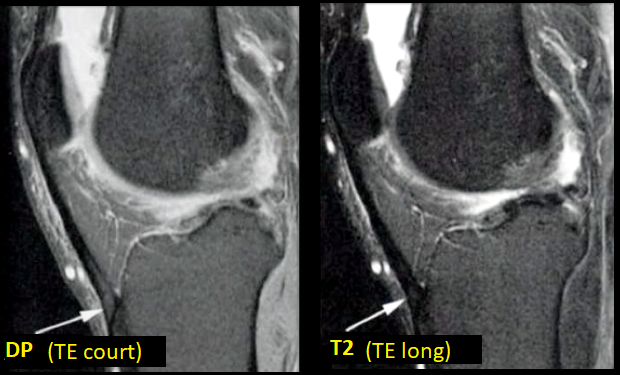

- Séquences avec TE court (T1, DP, GRE)

- Disparait avec un TE long (T2)